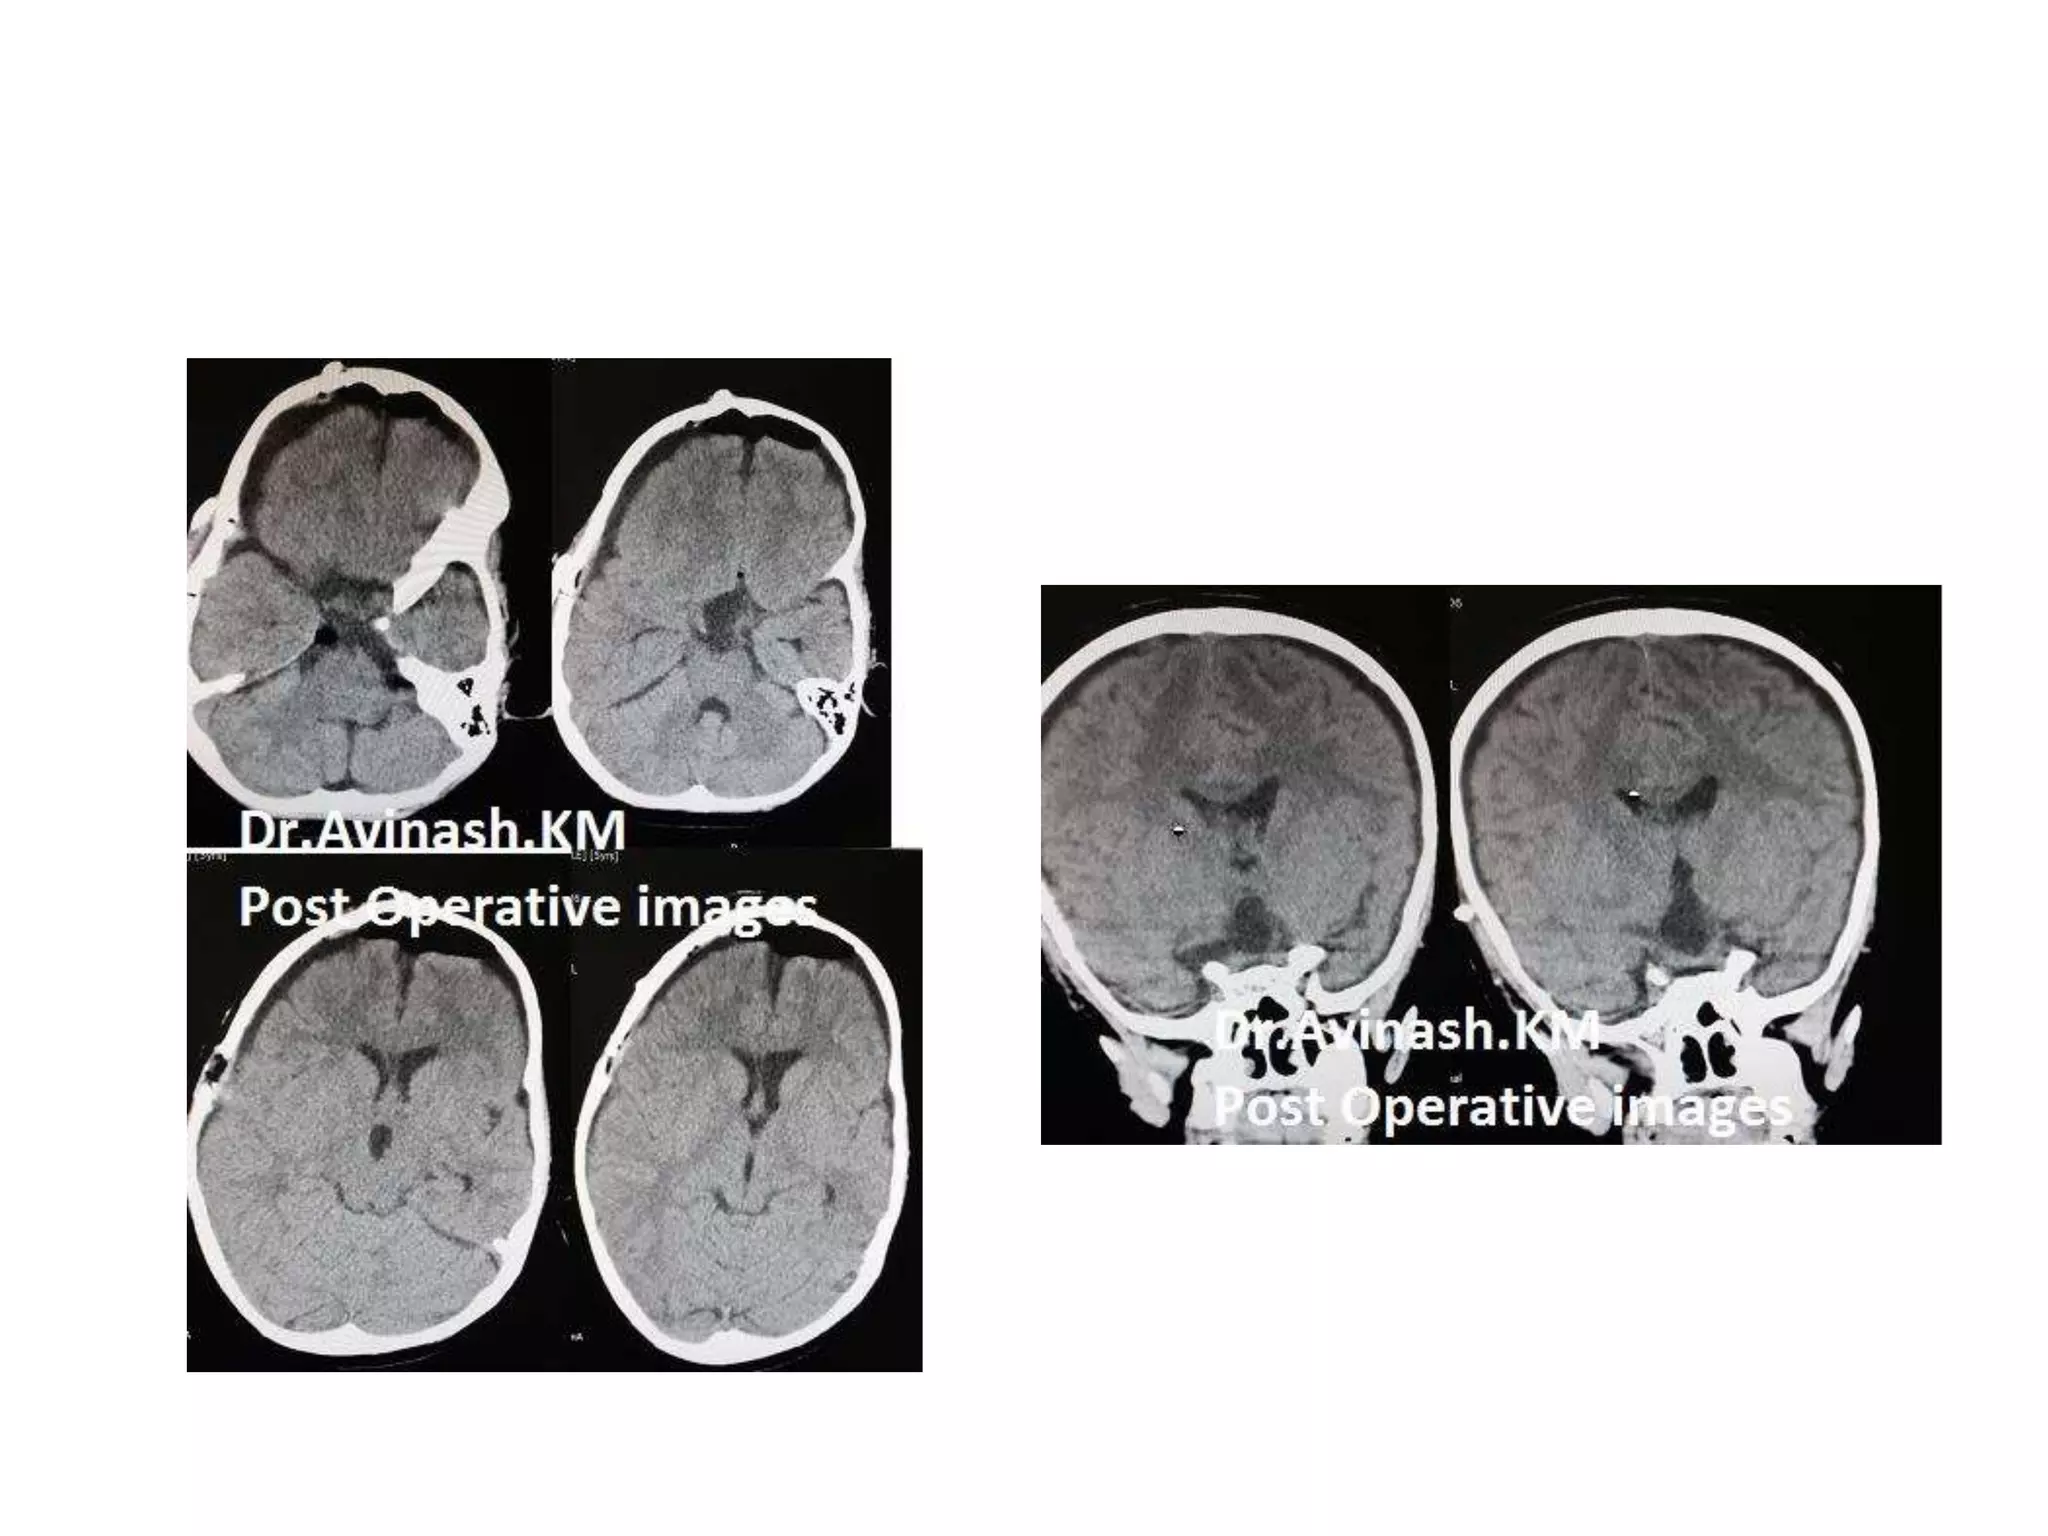

Craniopharyngioma

CRANIOPHARYNGIOMAS-Removal corridors.